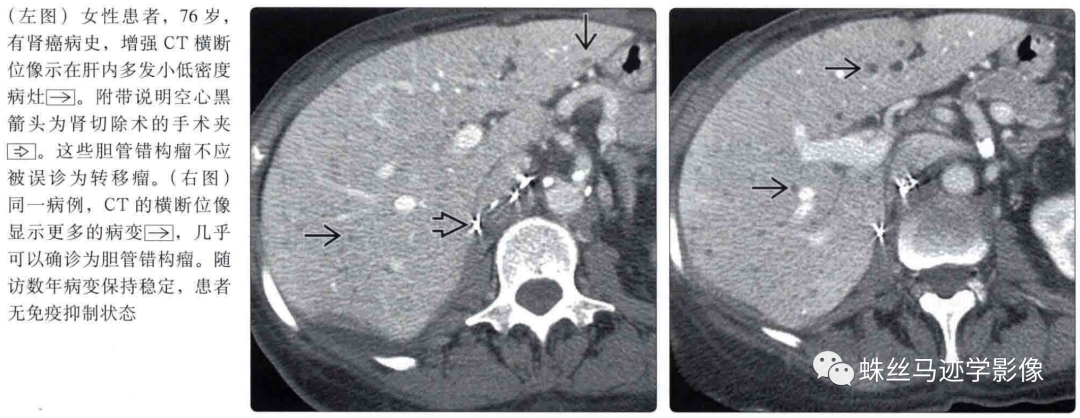

肝内胆管错构瘤和先天性肝内胆管囊状扩张症(Caroli病)-2